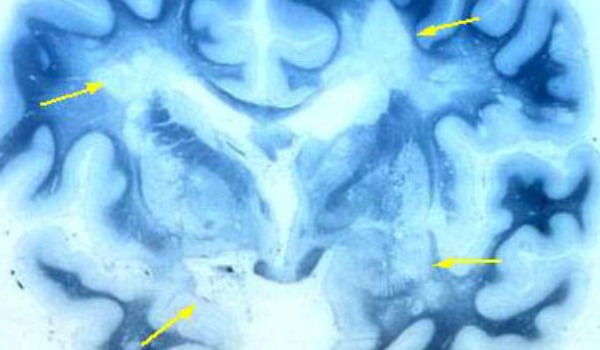

Scleroza multiplă este una dintre cele mai comune boli autoimune care afectează sistemul nervos. Această afecţiune afectează de două ori mai multe femei decât bărbaţi, iar în majoritatea cazurilor pacienţii se confruntă cu stări de oboseală, dureri, pierderea mobilităţii şi apariţia problemelor de vedere. Afecţiunea apare atunci când sistemul imunitar este afectat şi atacă sistemul nervos.